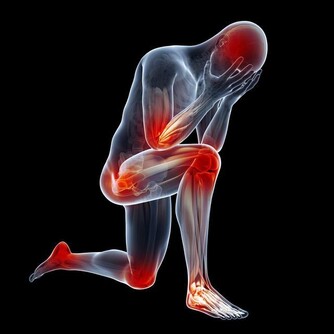

體表皮膚的疼痛部位往往就是皮膚受傷的部位,

但是內臟的病變引起的疼痛就不像體表的皮膚那樣定位準確,

往往會表現為反射痛或牽涉痛,疼痛的部位並不是病變的部位。

肝癌引起右肩部疼痛就是牽涉痛,

這可能是肝癌壓迫附件的膈肌或肺部以下的肌肉神經所引起的。